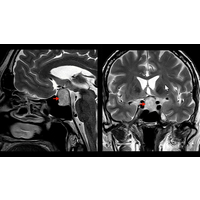

Einer Schilddrüsenüberfunktion können verschiedene Ursachen zugrunde liegen. Zum einen ist dies eine vermehrte Eigenproduktion von Schilddrüsenhormonen bei autonomen Knoten (mit und ohne Vergrößerung der Schilddrüse). Alternativ können Schilddrüsen-spezifische Autoantikörper (TRAK= TSH-Rezeptor-Antikörper bei Morbus Basedow, Abbildung 1, nächste Seite) zu einer dauerhaften Aktivierung des TSH-Rezeptors an den Schilddrüsenzellen führen und anstelle des physiologischen Hormons TSH die Schilddrüsenhormonproduktion aktivieren.

Abbildung 1: Sonografie der Schilddrüse bei Morbus Basedow, die untere Abbildung zeigt die vermehrte Durchblutung mittels Dopplersonografie